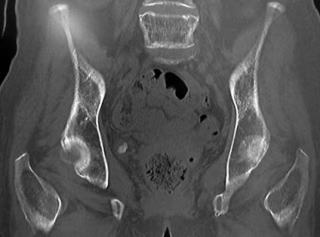

幸い当院リハビリ科に転院時に骨盤骨のCTが撮影してあり、そこに結石が映っていました。

CT(骨条件)

結石の形態は、ちょうど尿道カテーテルのバルーンに付着した結石を考える形です。